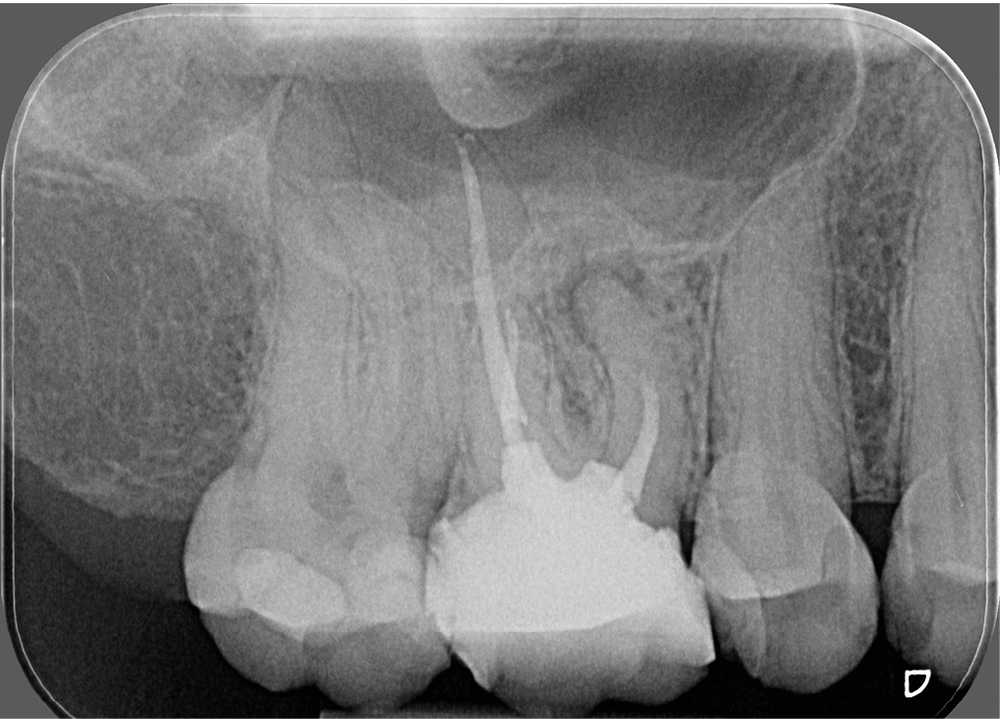

- un retraitement orthograde présente un mauvais rapport bénéfice-risque : par exemple, la présence d’un tenon dont la dépose pourrait fracturer la dent (fig. 2a-b) ;